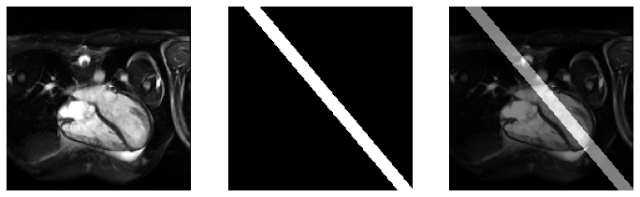

This segmentation task can be performed for the 2Ch line prediction case. In the 4Ch cardiac image, pixels could be classified as belonging to one of two classes – the 2Ch line or the background. Using a supervised learning approach, I trained a convolutional neural network called the “UNet” to predict a mask for the 2Ch view and using this mask, I reconstructed the predicted 2Ch line.